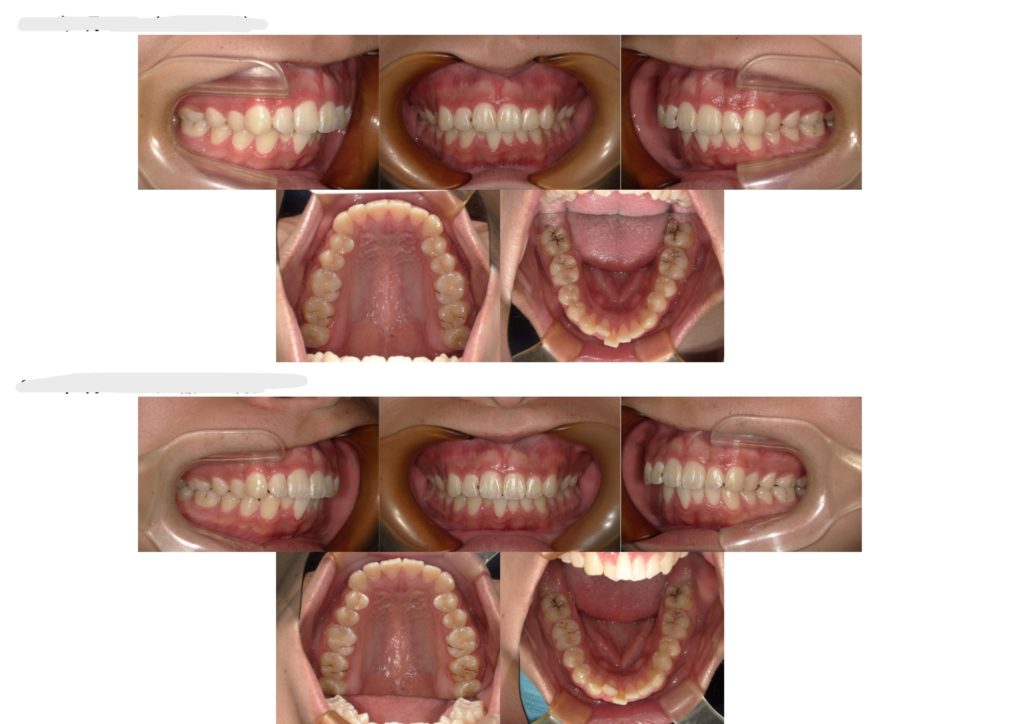

当院にて部分矯正にて治療された10代男性の症例になります。

上の前歯が出ているのが気になるとのことでご来院いただきました。治療期間は約6か月でした!

今回の症例は、ブラケット装置を上顎のみ付けて治療を行いました。

こちらが保定期間の比較写真になります。

リテーナーを毎日しっかり使用してくれていたので、綺麗な状態のまま!口腔習癖もなく、終了時とほぼ変わらずで保定期間を終えられました😊!ご協力いただきありがとうございました!